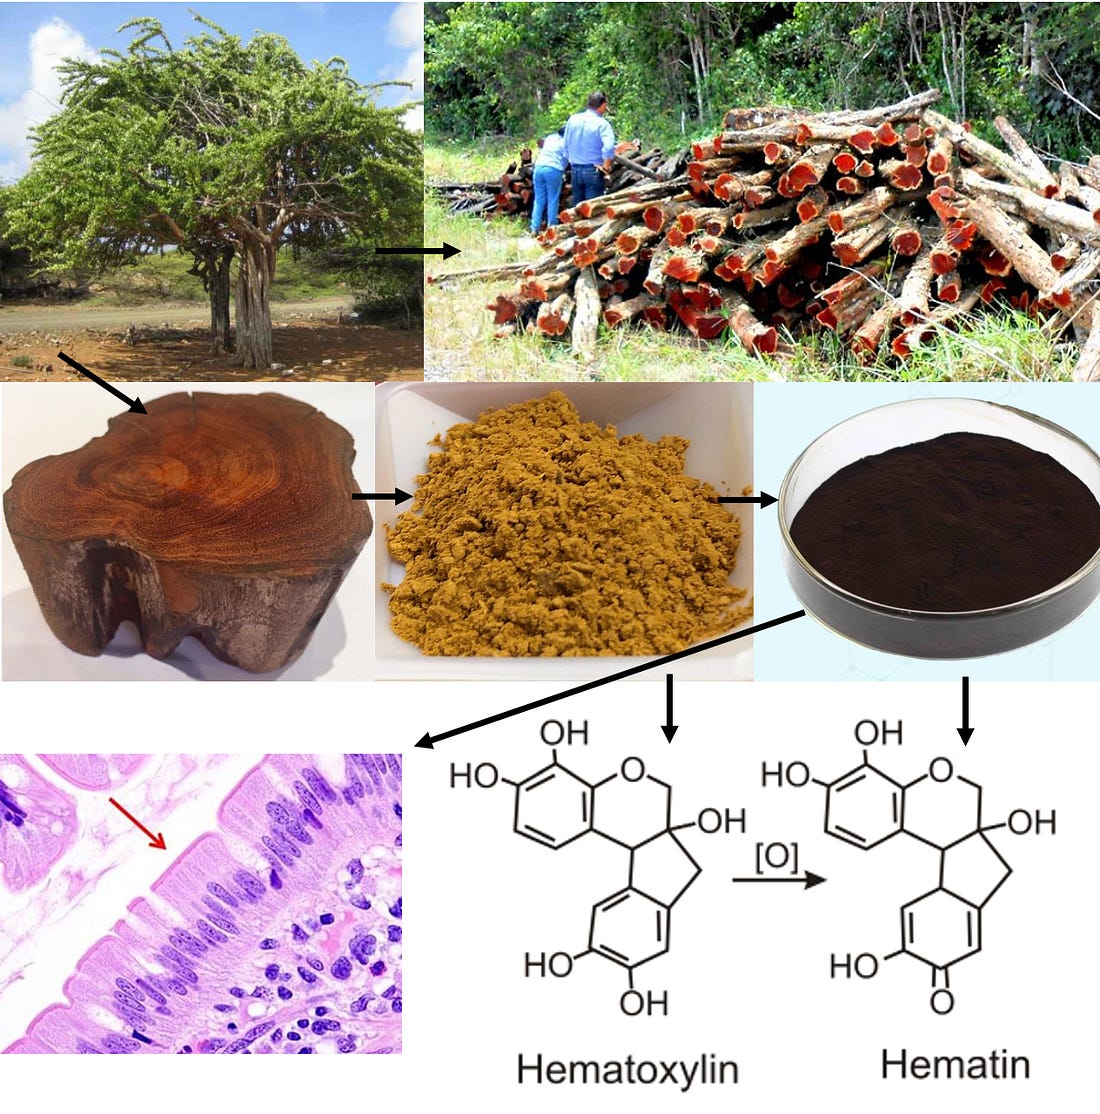

As such, I recently published an article on DMSO’s remarkable properties for treating cancer and cited hundreds of studies showing that: •DMSO causes a wide range of cancer cells to transform back into normal cells. Remarkably, despite DMSO’s anticancer properties routinely being used in lab experiments (including those seeking to find anticancer agents with those same anticancer properties), the cancer field has a striking blind spot to DMSO’s use, so in the existing literature, it is almost never discussed as a potential therapeutic. Of these many uses, I believe the two most noteworthy are DMSO’s ability to mitigate the challenging complications of cancer (e.g., cancer pain or protecting healthy tissue from radiation therapy) and its ability to potentiate other anti-cancer agents. Combination DMSO TherapiesOne of the major advantages and risks of DMSO is that it can bring substances through the skin and significantly increase their potency in the body. On one hand, this is quite advantageous as it makes it possible to administer things which would otherwise require injections through the skin and for much lower doses of them to be needed to get results (e.g., as I showed here, antimicrobials mixed with DMSO are often able to treat a wide range of chronic infections which otherwise resist antimicrobial therapy). However, on the flip side, it greatly increases the risk of toxicity, either by accidentally bringing toxic compounds (e.g., pesticides) into the body that were on the skin prior to applying DMSO (or that were touched afterwards), or increasing the potency of a drug taken in combination with it. Note: it is well known that healthcare workers who routinely administer chemotherapy periodically have accidental exposures to it (e.g., via vapor inhalation), so organizations like the CDC and NIOSH have worker guidelines about it (as these exposures increase the risk for a variety of issues including cancers). Since DMSO will cause chemotherapy drugs it is mixed with to be absorbed through the skin, it is crucial to be extremely cautious when administering it with chemotherapy drugs (particularly when applying it topically). Since natural therapies are typically much less toxic than conventional pharmaceuticals and easily available (rather than requiring a prescription) over the years, people have tried combining DMSO with many of them and frequently found significant advantages from mixing them together DMSO. This also holds true in the field of cancer care, and from reviewing all of the ways in which DMSO has been used to treat cancer, I believe the most promising applications (and which had the strongest data supporting their human use) came from DMSO being used in combination with another natural therapy. Unfortunately, the number of substances DMSO can be combined with is almost endless, and as such, the DMSO field has only scratched the surface of what it can be combined with to treat cancer. Many highly potent cancer treatments are likely waiting to be discovered once the right things are combined with DMSO. Note: somewhat analogously, in the hundreds of studies I identified that examined if DMSO could differentiate a specific tumor type or improve a particular cancer-related gene (or protein), most of them found DMSO did create an improvement. As such, many other aspects of cancer would likely also be seen to improve following DMSO if they were to be tested. HematoxylinHematoxylin is a powder obtained from the logwood tree (e.g., grinding the heartwood up, boiling it in water to dissolve the hematoxylin present, and evaporating that mixture so only the powder remains). That tree is native to Central America and was originally used by the Mayans to stain cotton and as a medicinal (e.g., to treat diarrhea and dysentery). After its discovery by the Spanish in 1502, a massive market for it quickly developed due to the textile industry’s need to establish a dependable dye. Before long it began to be mixed with a variety of metal salts so it would remain in fabric (and not wash out). Since many cellular processes are transparent and hence difficult to see without dyes that can stain them, much later (around 1830) hematoxylin began to be used in pathology where it was discovered (once oxidized into hematein and attached to a metal salt) it was remarkably effective for staining many components of cells including DNA. In turn, because of how well it works, almost two hundred years later, it remains one of the primary stains used in pathology to evaluate tissue (it’s the “H” in H & E stains). Note: like hematoxylin, DMSO is also obtained from trees. Because each of these compounds is so widely used, they are also very affordable. Tucker’s DiscoveryCurrently,